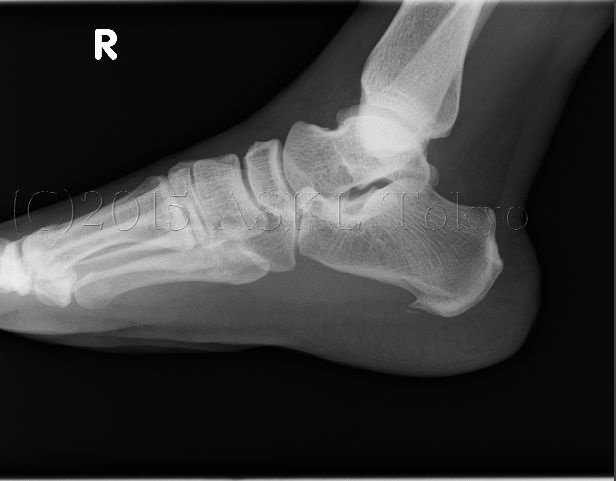

踵の痛みの出る代表的な箇所は、左写真(踵骨棘)の様に踵に棘のような骨ができてそれが足の皮下組織や神経を傷める

踵骨棘の治療のこんななところは、レントゲンでは2次元のために棘の方法と深さが負からないためにどの方向に踵が倒れると痛いかを知ることが難しい